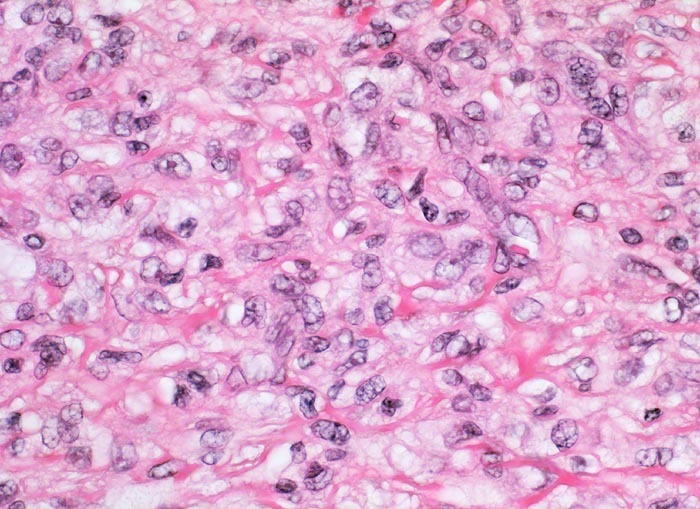

Benignes fibröses Histiozytom

Fibroblastäre Zellen umgeben von einem kollagenfasrigen Stroma. Das reichlich vorhandene Zytoplasma ist vakuolisiert. Die Zellkerne sind rundlich bis länglich mit feinem Chromatin und enthalten einen kleinen eosinophilen Nukleolus.

Derber indolenter rotbrauner Knoten am Arm, Durchmesser des Knotens 5mm.

Histologie

400